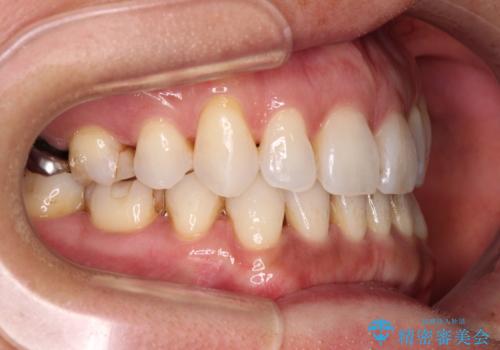

抜歯矯正の後戻りをインビザライン・ライトで解消

- 下顎前歯を中心に、以前行った矯正治療の後戻りが気になるとのことで来院された患者様です。

後戻りは軽度であったため、インビザライン・ライトにて治療を行うこととしました。

矯正治療後は、再度後戻りすることを極力回避するために、下顎前歯の舌側を細いワイヤーを用いて保定することとしました。